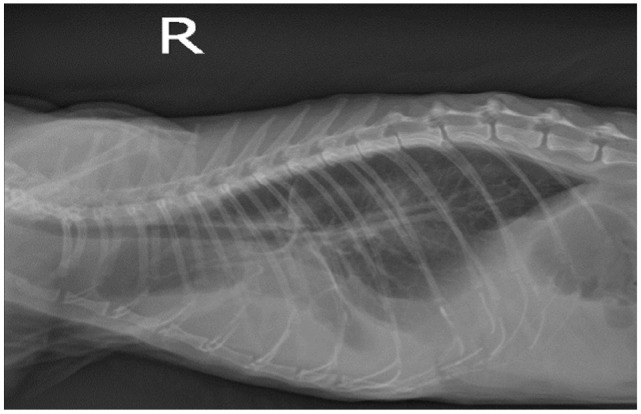

Case summary: A 7-year-old female spayed domestic shorthair cat was presented to our hospital with a 2-day history of anorexia, dyspnoea and lethargy. Blood tests revealed mild anaemia (packed cell volume [PCV] 22.4%) and the biochemistry panel was unremarkable. Thoracic radiographs and echocardiography showed the presence of pericardial effusion with cardiac tamponade as well as pleural effusion. During the initial attempt at pericardiocentesis, a small sample was obtained, sufficient only for fluid analysis and cytology. Subsequently, the pericardial effusion immediately resolved, presumably owing to the drainage of pericardial fluid into the pleural space. Thoracocentesis was then performed, yielding 50 ml of fluid. The analysis of the fluid was consistent with a protein-rich transudate associated with macrophagic-neutrophilic inflammation in both sampled areas. PCR was positive for Bartonella henselae in the pleural/pericardial fluid pool and peripheral blood. Bacterial culture was negative and feline coronavirus real-time PCR was negative. The patient was treated with marbofloxacin 5 mg/kg PO q24h for 5 weeks. No clinical signs were reported at this time; however, blood B henselae PCR remained positive. Treatment was changed to doxycycline at 5 mg/kg PO q12h for 6 weeks. The cat remained subclinical throughout the treatment, and a blood PCR after 6 weeks yielded negative results.

Relevance and novel information:  To the best of the authors' knowledge, the present clinical findings related to B henselae infection in a cat without concurrent heart failure have not been previously documented. This clinical case highlights the need to include Bartonella species as a differential diagnosis in cats with protein-rich transudate effusions associated with neutrophilic-macrophagic inflammation and fever.